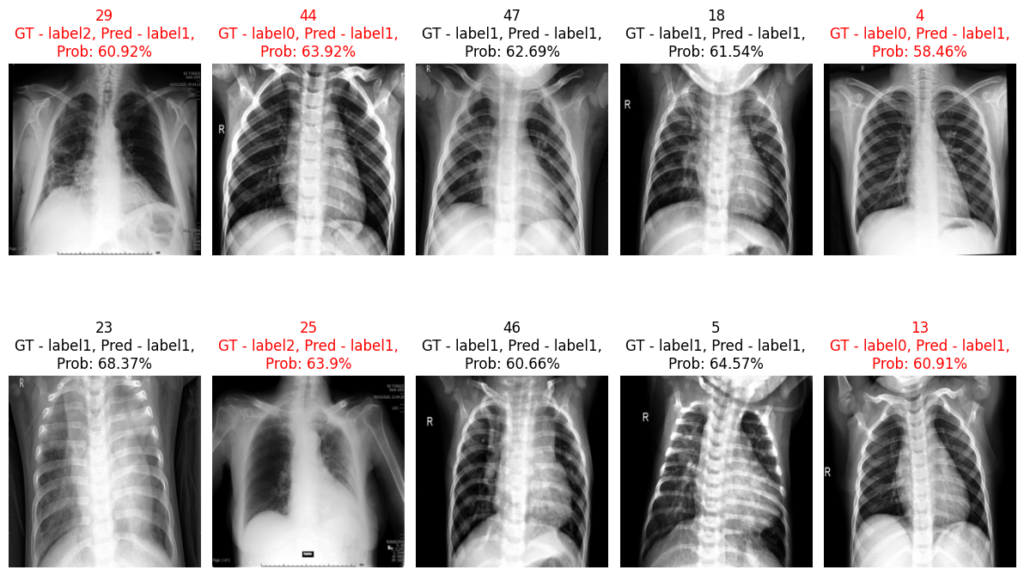

Predictions: